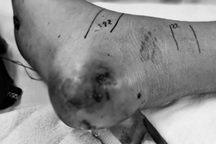

Ngày 21/12, bác sĩ Khoa Chấn thương - Chỉnh hình - Bỏng, Bệnh viện Sản Nhi Nghệ An đã điều trị thành công cho bé trai X.B.C. (8 tuổi, huyện Tương Dương, Nghệ An) bị hoại tử phần mềm toàn bộ mu bàn tay và mặt cẳng tay trái nghi do bị rắn cắn.

Bé C. được điều trị tại khoa Chấn thương - Chỉnh hình - Bỏng, Bệnh viện Sản Nhi Nghệ An (Ảnh: Hoàng Yến).

Sau khi tiếp nhận, các bác sĩ khoa Chấn thương - Chỉnh hình - Bỏng đã nhận định đây là trường hợp hoại tử mô mềm, nghi do nọc độc của rắn. Quan sát thấy bệnh nhi tỉnh táo, không sốt, tuy nhiên phần mềm vùng ngón thứ 2, mu bàn tay, các ngón tay còn lại và mặt sau cẳng tay trái bị sưng nề, hoại tử, kèm viêm mủ, đau nhức nhiều và hạn chế vận động.

Trong quá trình mổ, các bác sĩ đã cắt lọc loại bỏ phần hoại tử vùng ngón tay và mu bàn tay, rạch rộng để dẫn lưu mủ vùng cẳng tay và để hở, thay băng hằng ngày.

Sau 2 tuần được điều trị tích cực, vùng khuyết da mu bàn tay và ngón tay sau cắt lọc hoại tử đã mọc tổ chức hạt sạch. Bé tiếp tục được chỉ định phẫu thuật lần 2 để khâu kín da vùng cẳng tay vá da dày che phủ vùng mu bàn tay và ngón tay.

Sau 7 ngày từ khi ca phẫu thuật lần 2 được tiến hành, da ghép vùng mu bàn tay và ngón tay của bệnh nhi đã bám tốt, hồng, vết mổ khâu da vùng cẳng tay khô, liền mép. Hiện tại, sức khỏe của bệnh nhi tiến triển tốt và được chỉ định xuất viện.